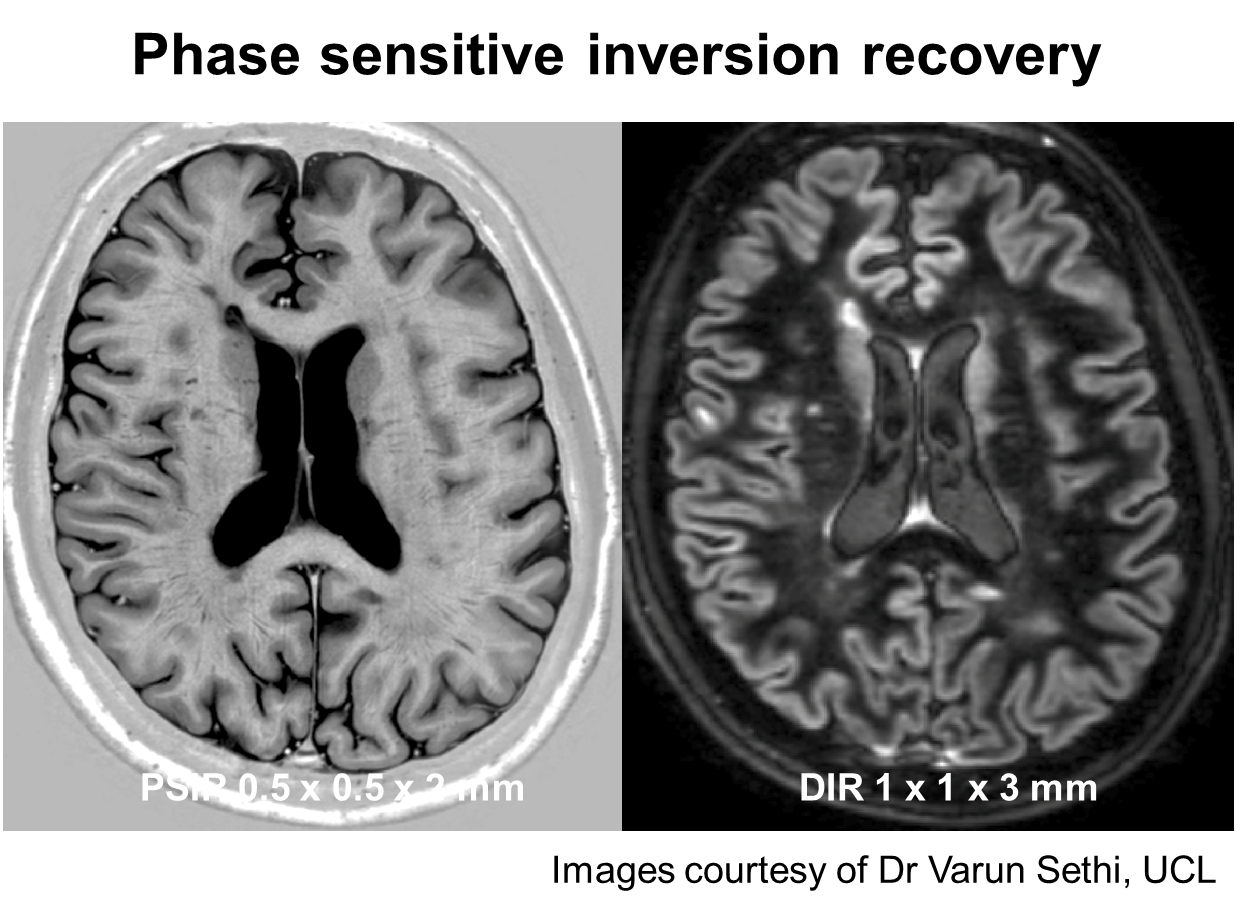

Multiple Sclerosis Research Guest post gray matter lesions in MS

Multiple Sclerosis Research Guest post gray matter lesions in MS Is Grey Matter Meaning Gray matter consists of densely packed neurons (nerve cells). The grey matter and the white matter. — what is gray matter? Grey matter in the brain consists of neuron cell bodies, dendrites, and synapses. — gray matter, also spelled grey matter (british spelling) and also called substantia grisea, is the part of the brain that is controlled by. Is Grey Matter Meaning.